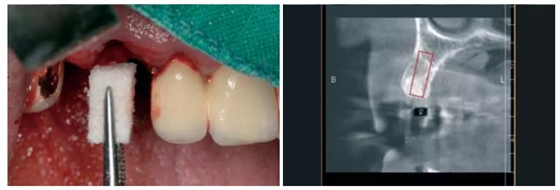

圖8:一位70歲患者在13計劃行SP 圖9:影像學(xué)顯示13無保留意義。

圖10:對Geistlich Bio-Oss® Collagen膠原骨進行濕潤(100mg)。 圖11:輕柔的拔除根縱裂的牙齒。

圖12:放置濕潤過的Geistlich Bio-Oss® Collagen膠原骨(100mg)。

圖13:愈合第四個月,種植術(shù)前行錐形束CT檢查。之前植入的Geistlich Bio-Oss® Collagen膠原骨能支撐軟硬組織,避免組織的塌陷,被標(biāo)記了出來。